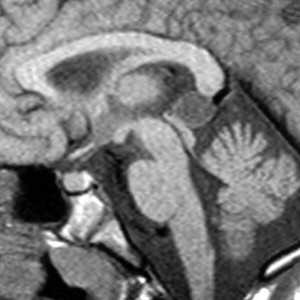

Дермоидные кисты встречаются реже эпидермоидных, составляя около 0,3 % от внутричерепных образований. Обычно выявляются в возрасте между 10 и 20 годами. Морфологически от эпидермоидов их отличает наличие эктодермальных элементов - волосяных фолликулов, потовых желёз и т.д. Типично они расположены по средней линии (в отличие от эпидермоидов, которые чаще внеосевые): в супраселлярной цистерне, субфронтально, вокруг моста и, очень редко парапинеально, периорбитально, в IV желудочке, в области конского хвоста и интрадиплоидно. От эпидермоидных кист на МРТ головного мозга их отличает только выраженная неоднородность структуры, кроме того, они всегда яркие на Т1-зависимых МРТ головного мозга за счёт большого содержания липидов. При разрыве и прорыве в субарахноидальное пространство в нём появляется уровень, на Т1-зависимых МРТ головного мозга светлый жир плавает на ликворе.

Дермоидные кисты встречаются реже эпидермоидных, составляя около 0,3 % от внутричерепных образований. Обычно выявляются в возрасте между 10 и 20 годами. Морфологически от эпидермоидов их отличает наличие эктодермальных элементов - волосяных фолликулов, потовых желёз и т.д. Типично они расположены по средней линии (в отличие от эпидермоидов, которые чаще внеосевые): в супраселлярной цистерне, субфронтально, вокруг моста и, очень редко парапиниально, периорбитально, в IV желудочке, в области конского хвоста и интрадиплоидно. От эпидермоидных кист на МРТ головного мозга их отличает только выраженная неоднородность структуры, кроме того, они всегда яркие на Т1-взвешенных МРТ головного мозга за счёт большого содержания липидов. При разрыве и прорыве в субарахноидальное пространство в нём появляется уровень, на Т1-взвешенных МРТ головного мозга светлый жир плавает на ликворе.